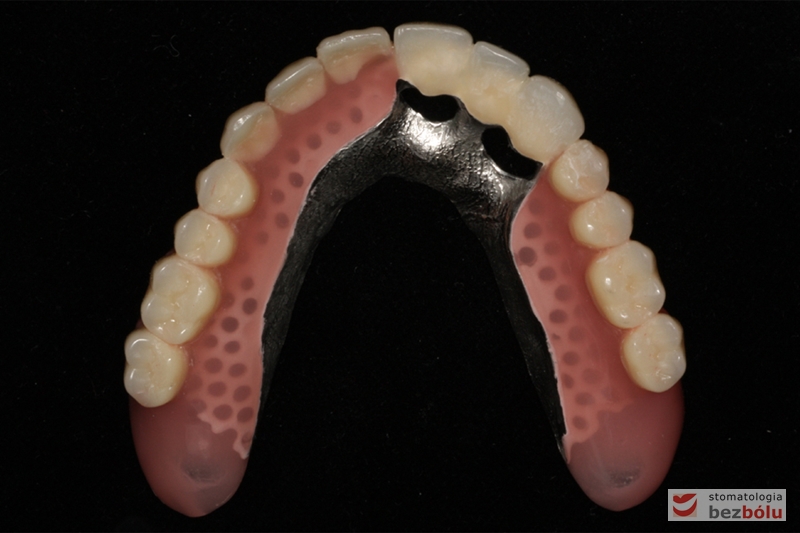

Odbudowa protetyczna szczęki - wykonana z kompozytu w wygodnym kształcie - tzw. "U-shape"

Odbudowa protetyczna szczęki – wykonana z kompozytu w wygodnym kształcie – tzw. „U-shape”